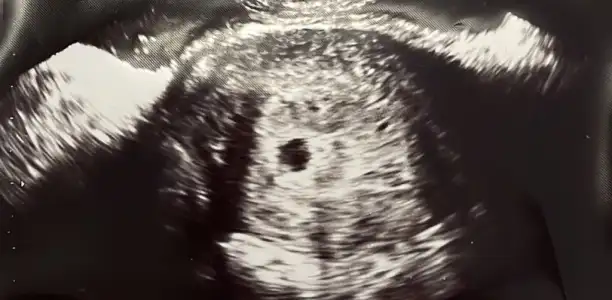

Merhaba kızlar biz bu sabah keseyi gördük.10mm ve 7 haftalık.çok şükür bir aşamayı daha atlattık.

Canım 7. Haftada kesenin 10mm olmasına normal dedi mi doktorun? Ben dün acile gittim normalde 7 haftalık gebeyim doktorumda pazartesi kontrolüm var. Acildeki doktor 10mm ölçüsü 5 hafta için geçerli dedi. İçimi huzursuz etti yarını zor bekliyorum doktoruma gitmek için

Ben yarın kalp atışı duymaya kendi doktoruma gidicem aslında ama dün kasık ağrım olunca acildeki doktor 10 mm lik kese 5 haftalıktır. Sen 5 haftalık gebesin kalp atışı duyamazsın dedi. Yolk saçınıda göremedi. Ama benim doktoruma göre şuan 7. Haftamdayım çok stres oldum. Boş gebelik mi diye düşünmeye başladım.

Benimde siyah beyaz olan 5. Haftamın ultrasonu. Renkli olan dün acilde doktorun çektiği ultrason yani 7. Hafta. Kesede büyüme var ama yolk saçını görmedi. Çok huzursuz oldum.